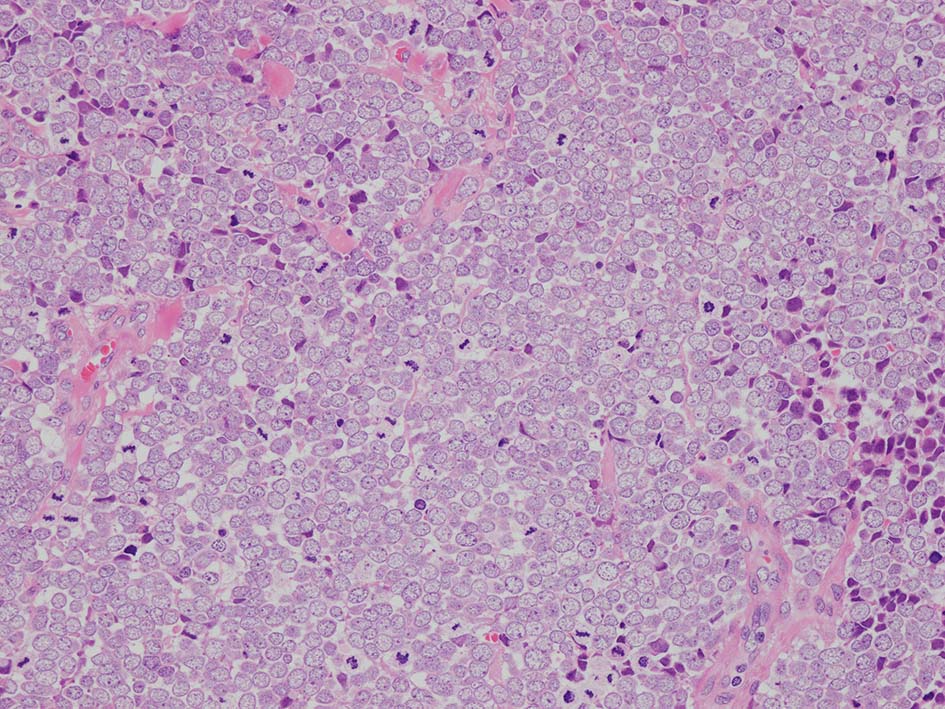

皮膚原発性Merkel細胞癌は 通常真皮を病変首座に増殖し, しばしば脂肪織まで浸潤する.

表皮とは連続性がなくGrenz zoneがみられるのが特徴であるが, 病理所見は多様であり, ときに表皮向性を示す症例やpagetoid patternを呈する症例もある.

典型的な腫瘍細胞は円形, 卵円形の比較的均一な形態で「salt-and-pepper」と称される微細顆粒状クロマチンを有する小型円形核をもつ. MCPyV陽性例が均一な小型円形核を呈する傾向があり, 陰性例では, 核多形性が目立つととする報告がある.

trabecular type, intermediate type, samll cell typeの3パターンの組織型に分類されているがしばしば混在している.

- intermediate typeではtrabecular, samll cell typeの中間の腫瘍細胞サイズを示す. 組織型としてはもっとも多い.

血管を間質にしてround cellsが索状に増殖する所見. rossett様配列がある. CK20は特徴的な dot-like patternを示す. クリックで大きな画像が見られます.